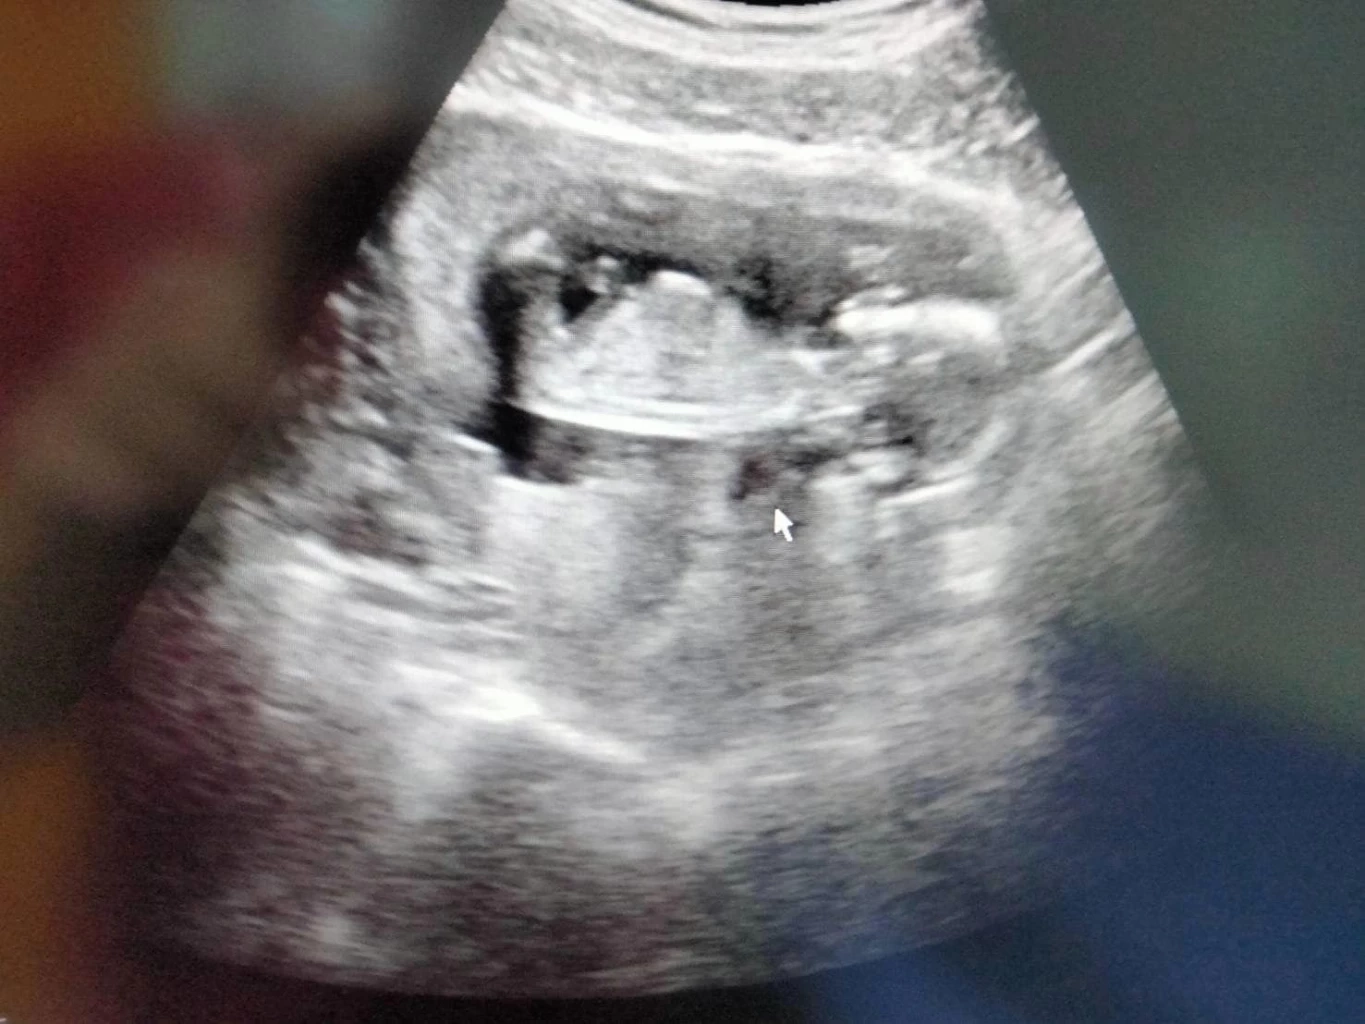

ล่าสุด โสรยา พรมหล้า ได้เปิดเผยสาเหตุของเรื่องดังกล่าวแล้ว โดยบอกว่าเป็นเพราะเธอตั้งครรภ์ได้ 3 เดือนแล้ว

"โสพึ่งรู้ว่าโสมีเจ้าตัวน้อยไม่กี่วันที่ผ่านมา โสไม่เคยรู้เลยว่าเจ้าตัวน้อยไปแข่งซีเกมส์กับโสช่วยพาทีมคว้าแชมป์ด้วย แถมยังร่วมฝึกซ้อมทีมชาติกับโสมาหลายเดือน และยังได้มีโอกาสเล่นกับทีมระดับโลกอย่างบราซิลด้วย มัมมี่ว่าถ้าหนูเกิดมา ไม่มีใครเล่นวอลเลย์เก่งเท่าหนูแน่เลย (ว่าแต่ทีมเราเล่น 7 คนในสนามจะผิดมั้ยเนี่ย)"